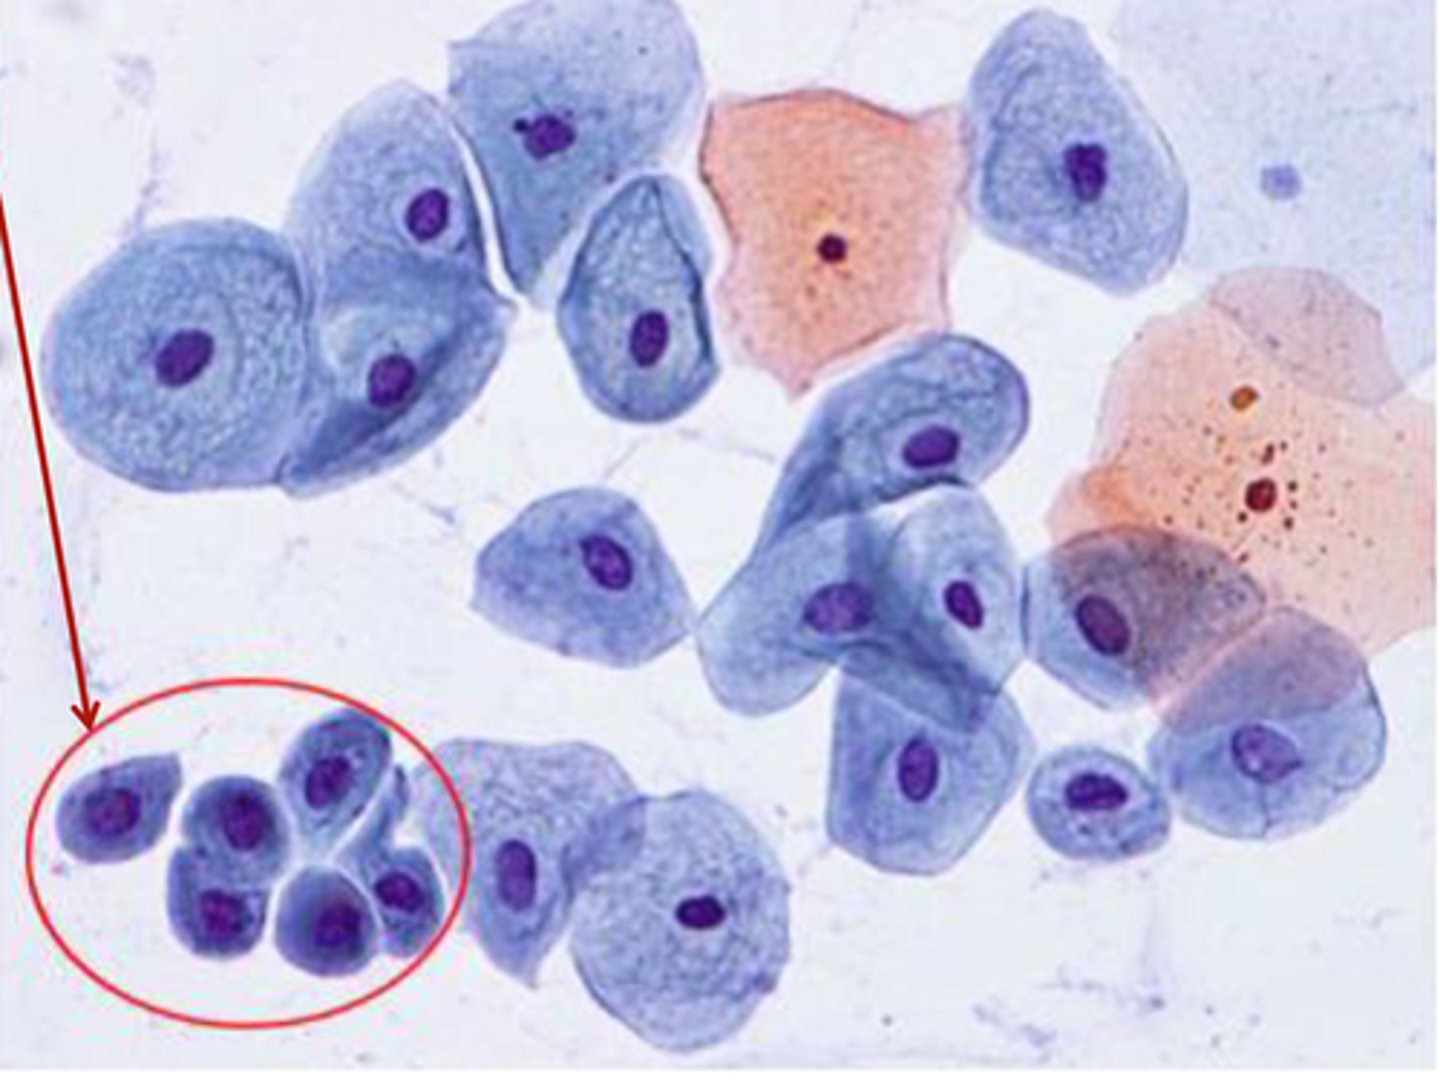

parabasal cell

vaginal cytology

round shaped and stippled nucleus

intermediate cells

vaginal cytology

angular shape and stipples nucleus

superficial cells

vaginal cytology

angular shape and pyknotic nucleus